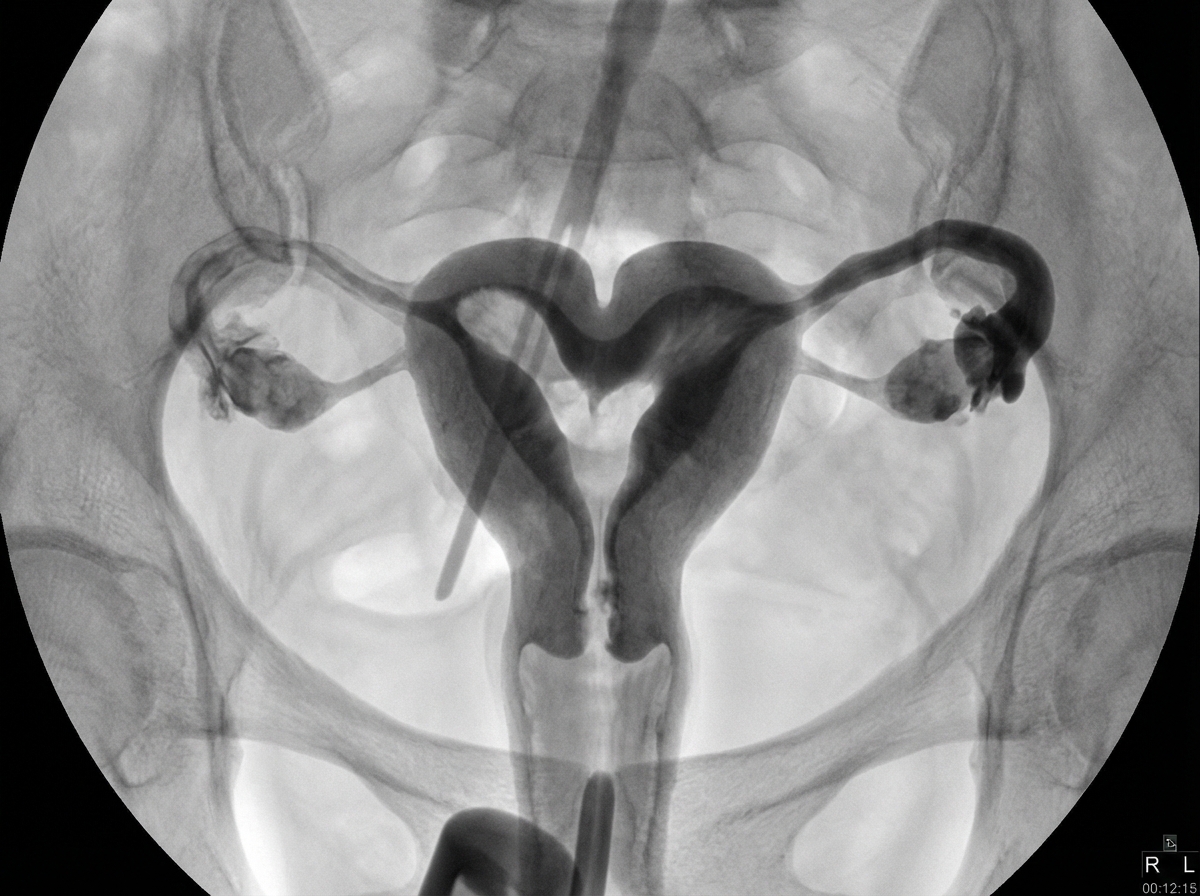

Explanation: ***Bicornuate uterus*** - Shows classic **heart-shaped external contour** with a **fundal cleft >1cm** and **intercornual angle >105°** on imaging - **HSG** demonstrates two separate uterine horns with **divergent lateral walls** and **MRI** confirms external fundal indentation *Unicornuate uterus* - Appears as a **single horn** with **banana-shaped** or **comma-shaped** configuration on imaging - Associated with **renal agenesis** on the same side and **rudimentary horn** may be present *Arcuate uterus* - Shows **minimal external fundal indentation <1cm** with **broad fundal impression** on imaging - **Intercornual angle <105°** and considered a **mild variant** with minimal clinical significance *Septate uterus* - Demonstrates **normal external uterine contour** with **internal septum** dividing the cavity - **MRI** shows **low signal intensity septum** and **intercornual angle <75°** differentiating from bicornuate